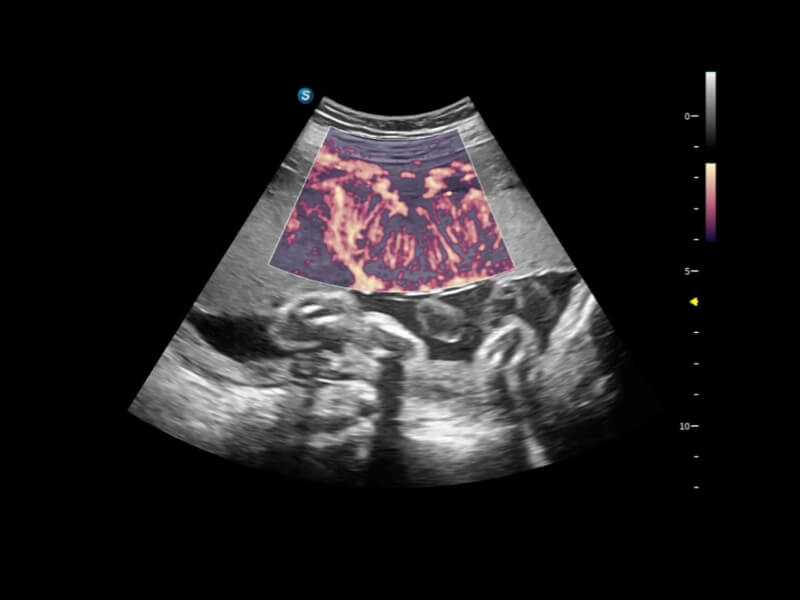

通过光照模型,使二维血流显示出立体的效果,增加血流的敏感性、成束性,减少外溢。可以和其他不同的血流技术联合使用,融合不同技术的优势。轻松应对微小血管,增强血流的立体效果,提升视觉敏感性。

通过创新的Matrix E自适应滤波算法,能有效滤除软组织和噪声信号,最大限度保留超低速微细血流的信号;结合超长时间域算法,极大提升细微血流的敏感性和空间分辨率,更真实的反应组织、包块的血流灌注情况。